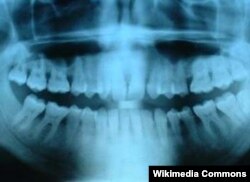

Тиштеги микробдорду жок кылчу робот-дарыгер

Пенсильвания университетинин (АКШ) инженерлери, биологдору жана стоматологдору робот-дарыгерлердин микроскопикалык системасын иштеп чыгышты.

Робот - дарыгерлер тиштин сыртында жана өзөк жагында иштөөгө ылайыкташкан. Мындай роботтор (анг. catalytic activity, орус тилинде каталитическая активность) биологиялык чел (биоплёнка) сыяктуу биригип алган бактериялардын уюткусун жок кылчу жөндөмгө ээ.

Аларды суу түтүктөрдү жана организмди дарылоо үчүн колдонулган түтүктөрдү (катетер) тазалоо, тишти зыяндуу батериялардан коргоо, анын ичинде тиштин тамырларын эндонтиялык инфекциялардан тазалоо, импланттарды таза кармоо үчүн да пайдаланса болот.

Биочел тиштин сыртында, муундарда же суу түтүгү, импланттар же катетер-түтүк сыяктуу предметтердин бетин каптайт да илешме жана былжырак матрица пайда болот. Матрица астындагы бактериялар тишти микробдорду жок кылчу заттардан коргойт. Ал бактерияларды тазалоо же жок кылуу жеңил эмес.

“Биопленкаларды жок кылчу азыркы ыкмалар эффективдүү эмес, - дейт проф. Майкл Ку. - Себеби, бир эле учурда калкан сымал матрицаны кыйратып, бактерияларды өлтүрүп, майдаланып кетчү азыктарды тазалай албайт. Робот-даргыгер береги үч ишти биопленканын изин калтырбай бир бүткөрөт”.